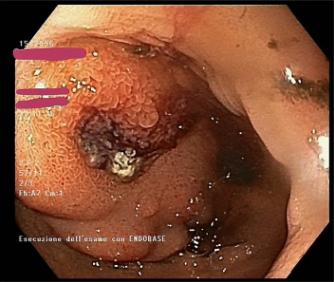

急诊上消化道内镜检查(GE)。GE显示胃内有血凝块,十二指肠管腔粘膜下突出病变,呈中央糜烂和可见血管,诊断为疑似胃肠道间质瘤(GIST)(图1)。

图1、GE示十二指肠管腔粘膜下突出病变,呈中央糜烂及可见血管,怀疑胃肠道间质瘤

将金属夹夹在出血血管上,并用肾上腺素粘膜下注射治疗病变。未进行活检以避免潜在的进一步出血来源。